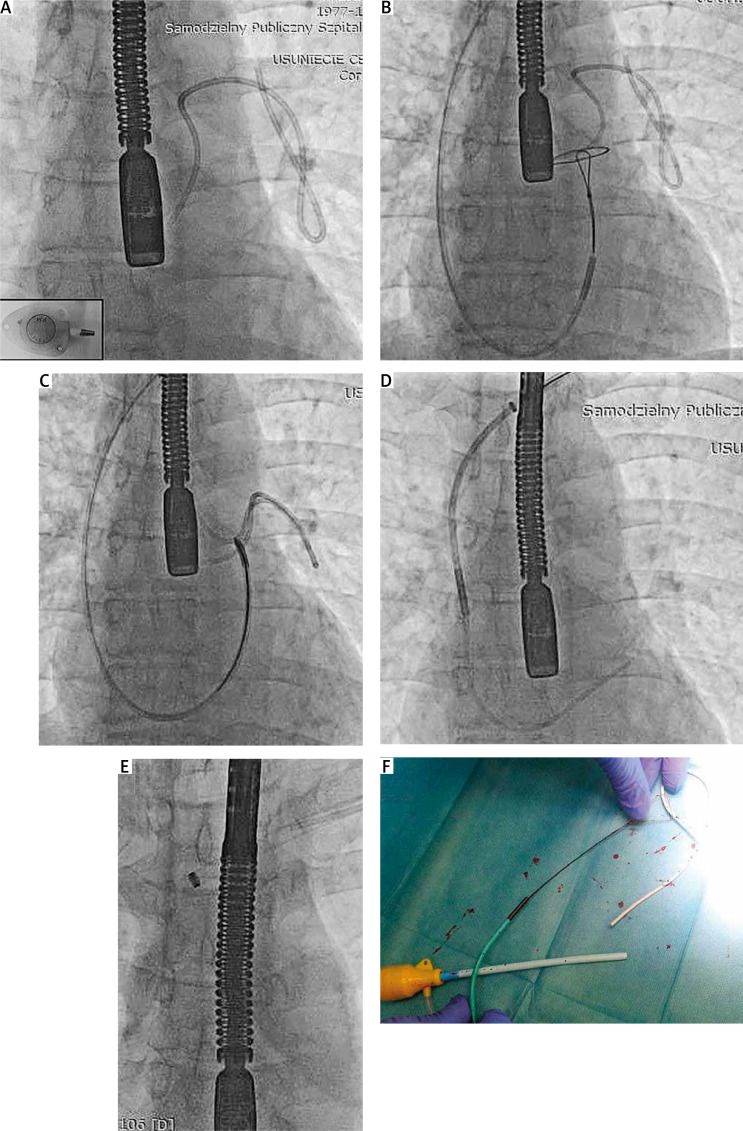

The use of venous access ports carries a risk of complications, including catheter fracture with migration of catheter fragments into the pulmonary arteries. Experience in removing broken catheters is limited and there are no special tools. We present 4 cases of catheter removal using the available lassos/lasso catheter and tools designed for transvenous lead extraction and coronary sinus lead implantation via a femoral and subclavian approach. All four procedures were successful and without complications.